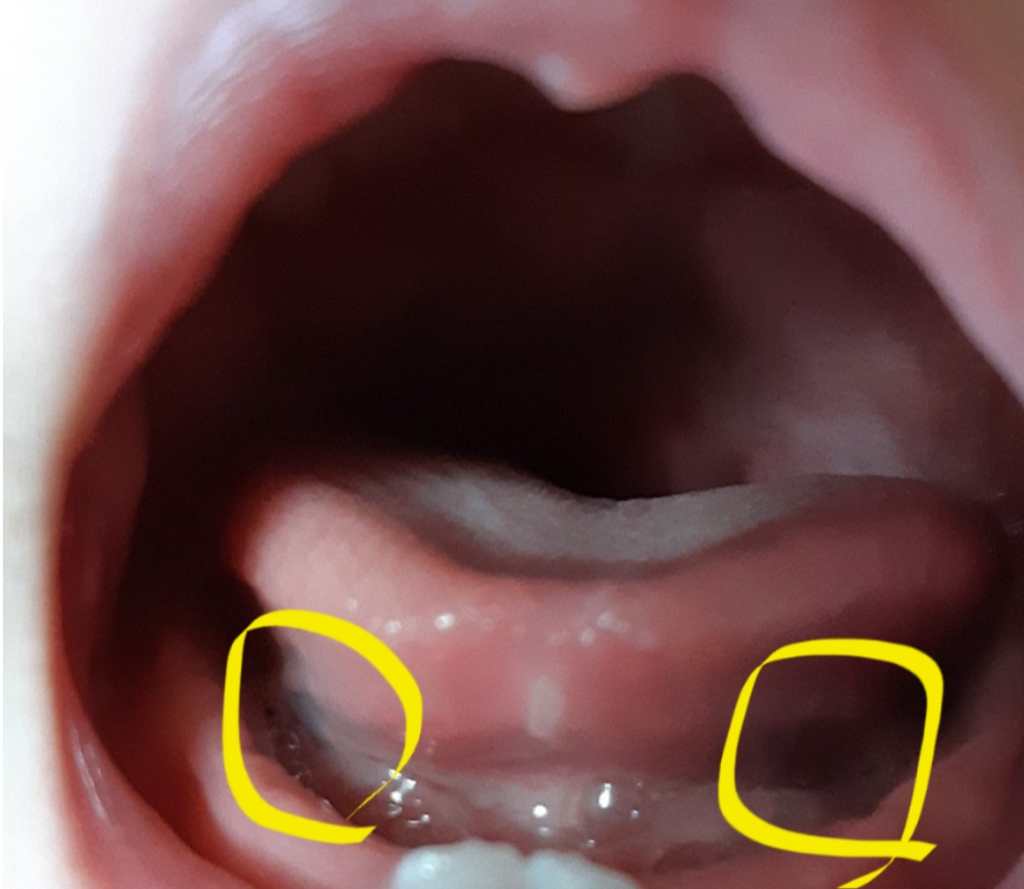

특별히 병적인 양상은 아닌 것 같습니다 혀 아래 부분 혈관이 지나가서 비쳐보이는 것입니다 정맥류나 뇌혈관흐름 이상 양상의 경우 더 명확한 증상이 있습니다

잇몸이 얇아서 안의 혈관이 비쳐서 푸른색을 띄는 것으로 보이는 것으로 정상이기에 걱정하지 않으셔도 됩니다.

치아가 나올때 그렇게 보일수 잇습니다. 잇몸을 뚤고 올라오면서 치아가 맹출되니 너무 걱정은 안하셔도 됩니다.